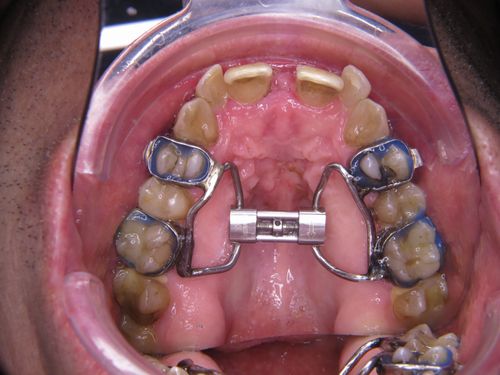

In einem ersten Behandlungsschritt wurden Ober und Unterkiefer verbreitert (transversaler Erweiterung). Allein dadurch zeigte sich schon eine Verbesserung der Atmung im Schlaf.